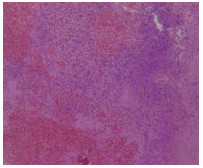

Primary biliary cholangitis with hepatic angiosarcoma: A case report

Jiamin ZHAO, Zhiyuan CHEN, Chengliang DING, Lili YUAN, Jingjing QIAN, Chunyang XU, Lingyun ZUO

2021, 37(10): 2411-2413. DOI: 10.3969/j.issn.1001-5256.2021.10.031

Abstract(818) HTML (189) PDF (2456KB)(80)

Abstract: